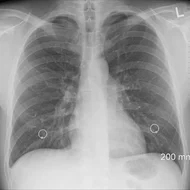

Március 23-án van A tuberkulózis (tbc) elleni küzdelem világnapja. A tuberkulózis más - néven gümőkor, tüdőbaj – egy baktérium által okozott megbetegedés, mely Magyarországon a védőoltásnak köszönhetően már csak ritkán fordul elő. A betegség megelőzhető és gyógyítható, azonban elhanyagolása halálhoz is vezet.